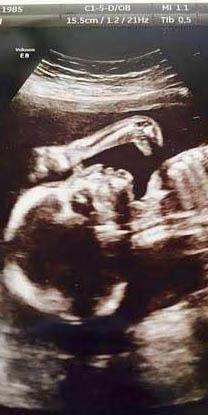

Al igual que cuando miramos las nubes y encontramos figuras en el cielo, un ultrasonido realizado a una mujer inglesa arrojó que su bebé era acompañado por un dinosaurio.

Leanne Sullivan, 29 años de edad que radica en Liverpool, Inglaterra, es la madre de la bebé Ruthie-Lou que es “cuidada” por un brontosaurio hasta el momento en que nazca.

La imagen fue captada cuando Leanne tenía 20 semanas de embarazo (en el mes de abril) y noto la presencia del “intruso”.

La pequeña Ruthie-Lou llegará probablemente a este mundo en cinco semanas, pero lo hará sin el dinosaurio.